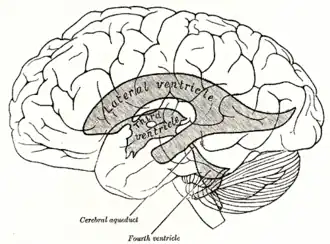

Scheme showing relations of the ventricles to the surface of the brain; oriented facing left. | |

The lateral ventricles are the two largest ventricles of the brain and contain cerebrospinal fluid.[1] Each cerebral hemisphere contains a lateral ventricle, known as the left or right lateral ventricle, respectively.

Each lateral ventricle resembles a C-shaped cavity that begins at an inferior horn in the temporal lobe, travels through a body in the parietal lobe and frontal lobe, and ultimately terminates at the interventricular foramina where each lateral ventricle connects to the single, central third ventricle. Along the path, a posterior horn extends backward into the occipital lobe, and an anterior horn extends farther into the frontal lobe.[1]